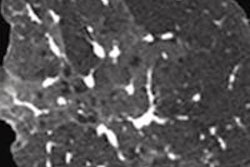

Finally, another image-analysis project is yielding new information about how diffuse lung disease affects pulmonary hypertension. Researchers from Japan are using 3D CT to probe the association between pulmonary hypertension, fibrosis, and emphysema. In patients with both diseases, it can be difficult to isolate the main contributor to pulmonary hypertension and, therefore, to determine the best course of care. Learn about their results by clicking here.